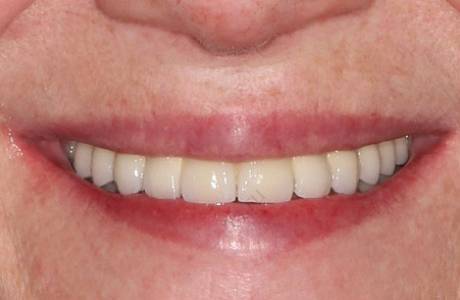

До лечения

Пациентка обратилась с жалобами на отсутствие жевательных зубов на нижней челюсти, неудовлетворительный внешний вид ранее изготовленных конструкции.

При остмотре также выявлено занижение высоты нижнего отдела лица и полное отсутствие прикуса, при том, что у пациентки изначально был патологический прикус с глубоким резцовым перекрытием.

Принято решение провести тотальную реабилитацию прикуса, восстановление эстетики и высоты нижнего отдела лица.

После лечения

На нижней челюсти установлены имланты. За время их приживления фронтальные зубы перелечены, восстановлены вкладками, на временных коронках зафиксирована нужная высота.

На все зубы были установлены коронки на основе диоксида циркония